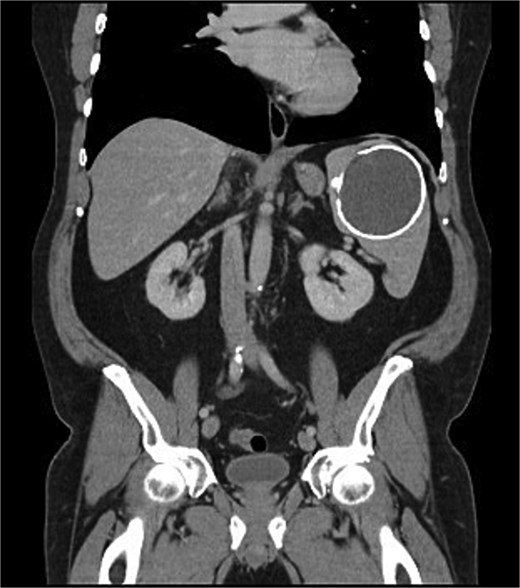

During this period of antiplatelet therapy, he experienced an episode of severe, atraumatic LUQ pain prompting presentation to the Emergency Department. A CT scan demonstrated a contained leak or haemorrhage from the large calcified splenic cyst within the subcapsular space, though no active haemorrhage was noted on arterial phase (Fig. 2). His white cell count and haemoglobin remained normal at 4.8 and 163, respectively, with no other biochemical abnormalities. He was monitored in hospital for a period before discharging once pain-free and 2 months later underwent an elective laparoscopic splenectomy. Intraoperatively, the spleen was noted to have areas of local inflammatory adhesions to the omentum and abdominal wall. Histology demonstrated an IPT like appearance with areas of necrosis and a florid xanthogranulomatous inflammatory process with focal staining for smooth muscle actin; Epstein–Barr Virus (EBV) testing was not performed. Postoperatively, his symptoms of abdominal pain, early satiety, and nausea had resolved, and an interval CT scan was scheduled in 6 months for surveillance given the atypical pathology.

Coronal portal venous phase CT scan of the abdomen and pelvis demonstrating the subcapsular leak.